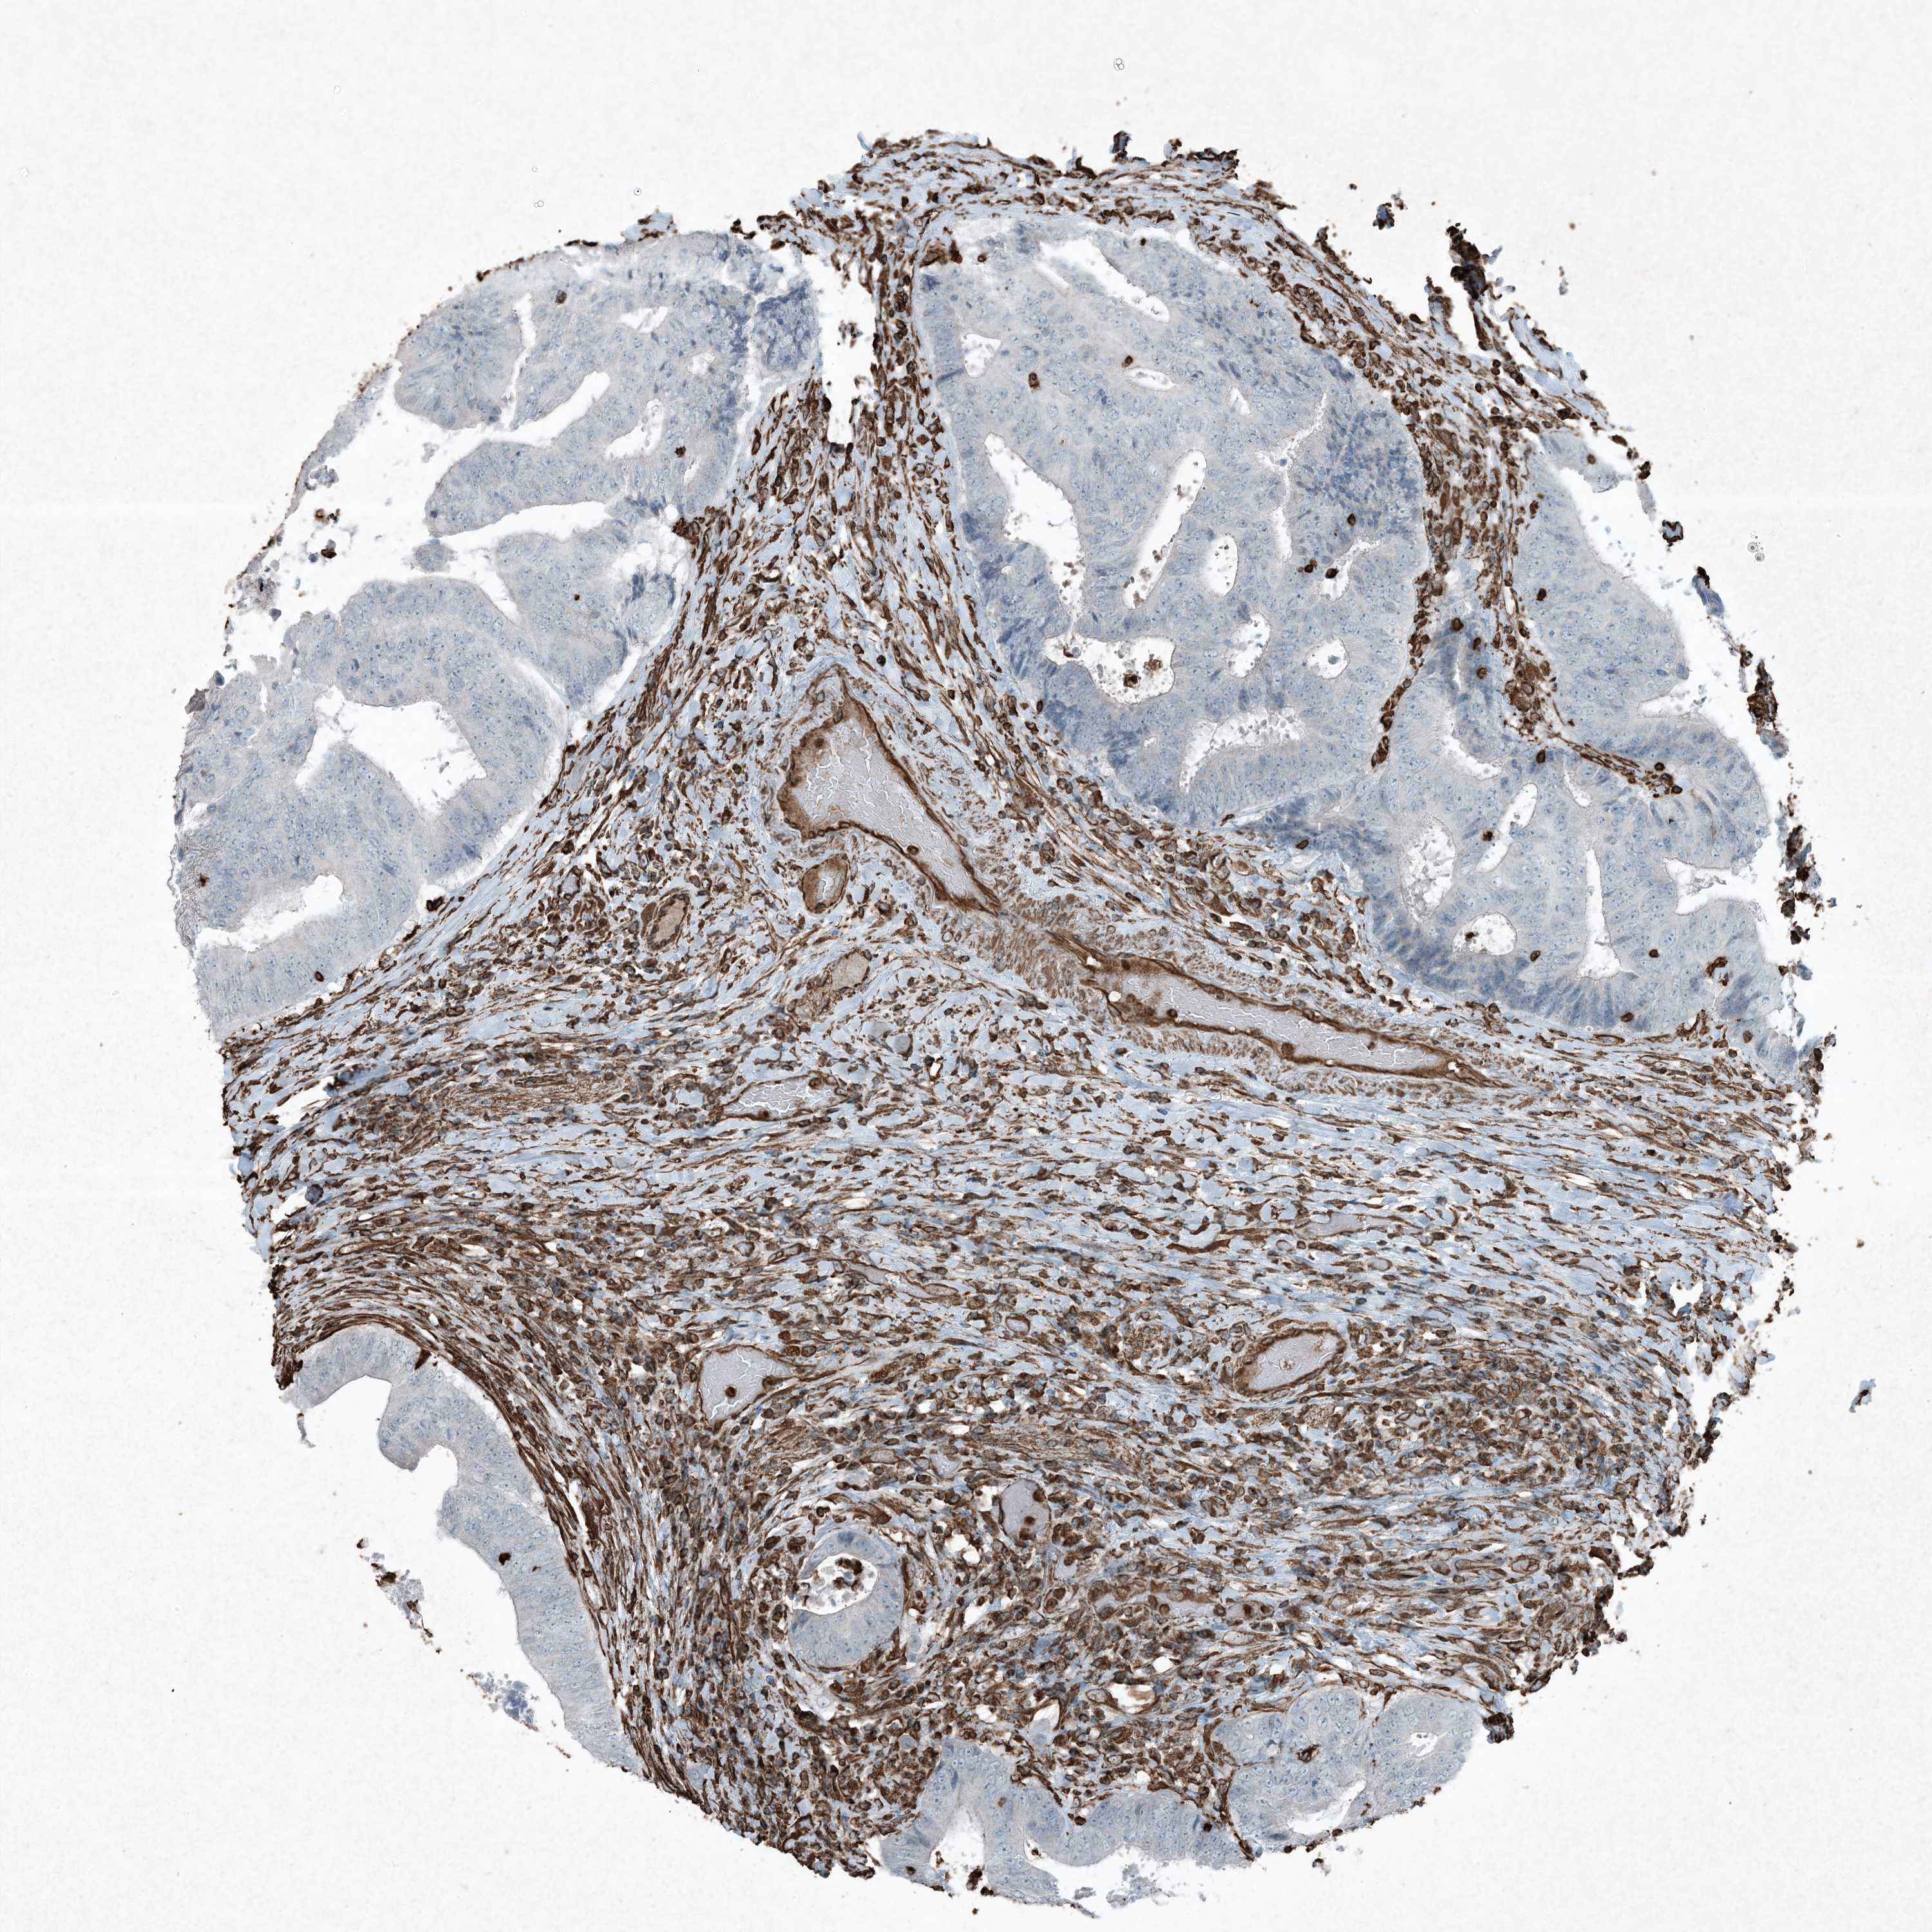

CANCER COLORECTAL CANCER Show tissue menu

COAD TCGA COAD VALIDATION READ TCGA READ VALIDATION PROTEIN COAD CPTAC PROTEIN EXPRESSION

ANTIBODIES

AND

VALIDATION